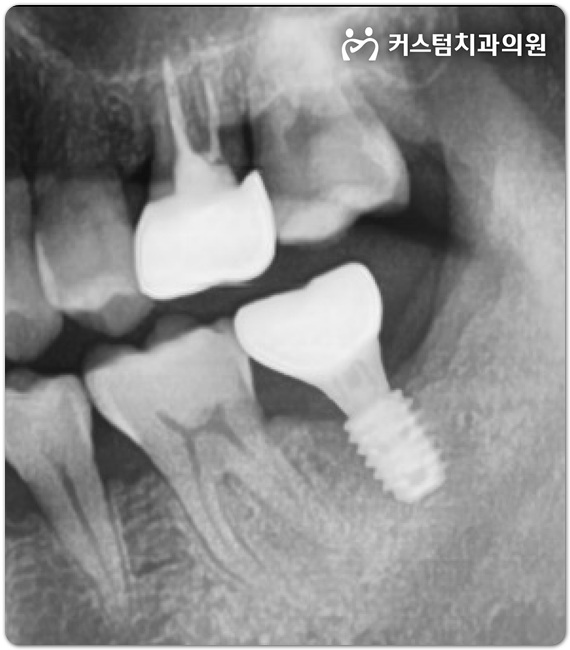

부천 임플란트 치과 전문의가 직접 진료한 사례

부천 임플란트 치과 전문의가 직접 진료한 사례 안녕하세요, 여러분. 보철과 전문의 직접 진료로 끝까지 책...